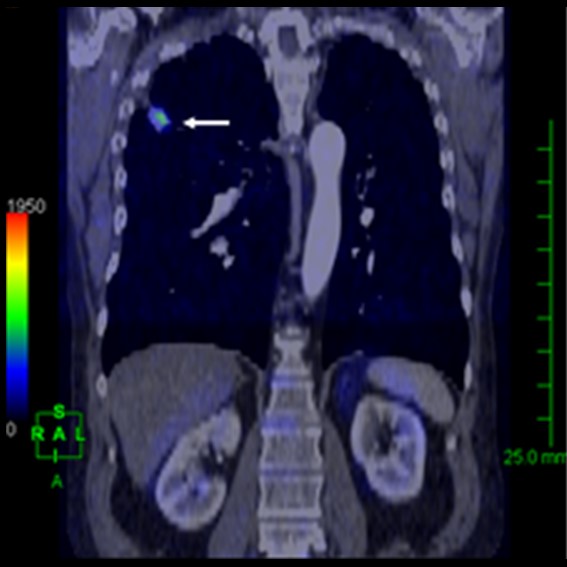

運用高科技尖端影像設備,提供貴賓精準的檢查、判讀、即時醫療、後續追蹤、健康管理或醫學中心轉介服務;從健檢診斷到後端治療,一條龍式服務。永越自成立以來,已服務超過16萬人次,每年通報件數超過千件,揪出包括:甲狀腺癌、肝腫瘤、肺癌、乳癌、子宮頸癌等重大異常的健康警訊,把握住早發現早治療的黃金關鍵。